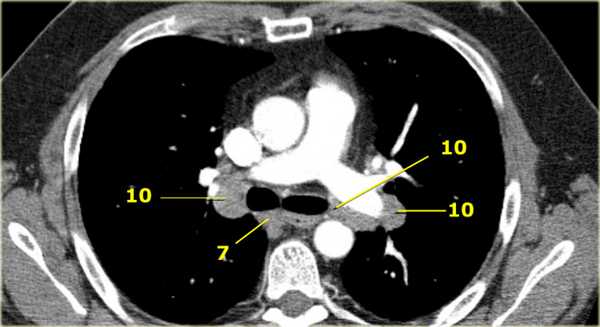

10. лимфатические узлы корня легкого

Лимфатические узлы корня расположены проксимальнее долевых узлов, но дистальнее медиастинальной дупликатуры и узлов промежуточного бронха справа.

Все лимфатические узлы 10-14 групп являются N1 узлами, так как они находятся вне средостения.

На левом изображении над уровнем легочного ствола представлены нижние паратрахеальные узлы слева и справа, так же здесь представлены узлы 3 и 5 групп.

Изображение слева выше уровня карины. Слева от трахеи 4L узлы. Обратите внимание что они расположены между легочным стволом и аортой, но не в аортопульмональном окне, потому что они лежат медиальнее артериальной связки. Лимфатические узлы латеральнее легочного ствола относятся к 5 группе.